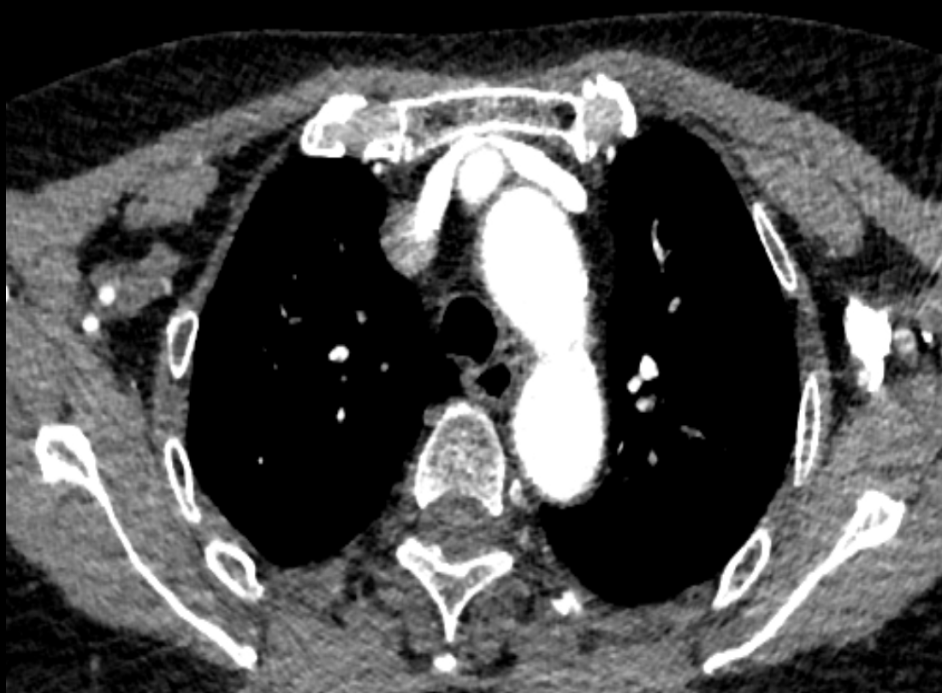

颈总动脉压迫左头臂静脉

左侧锁骨下静脉受主动脉弓挤压,导致对比剂冲入浅表静脉网中

左侧锁骨下静脉受主动脉弓挤压 血管充盈不佳